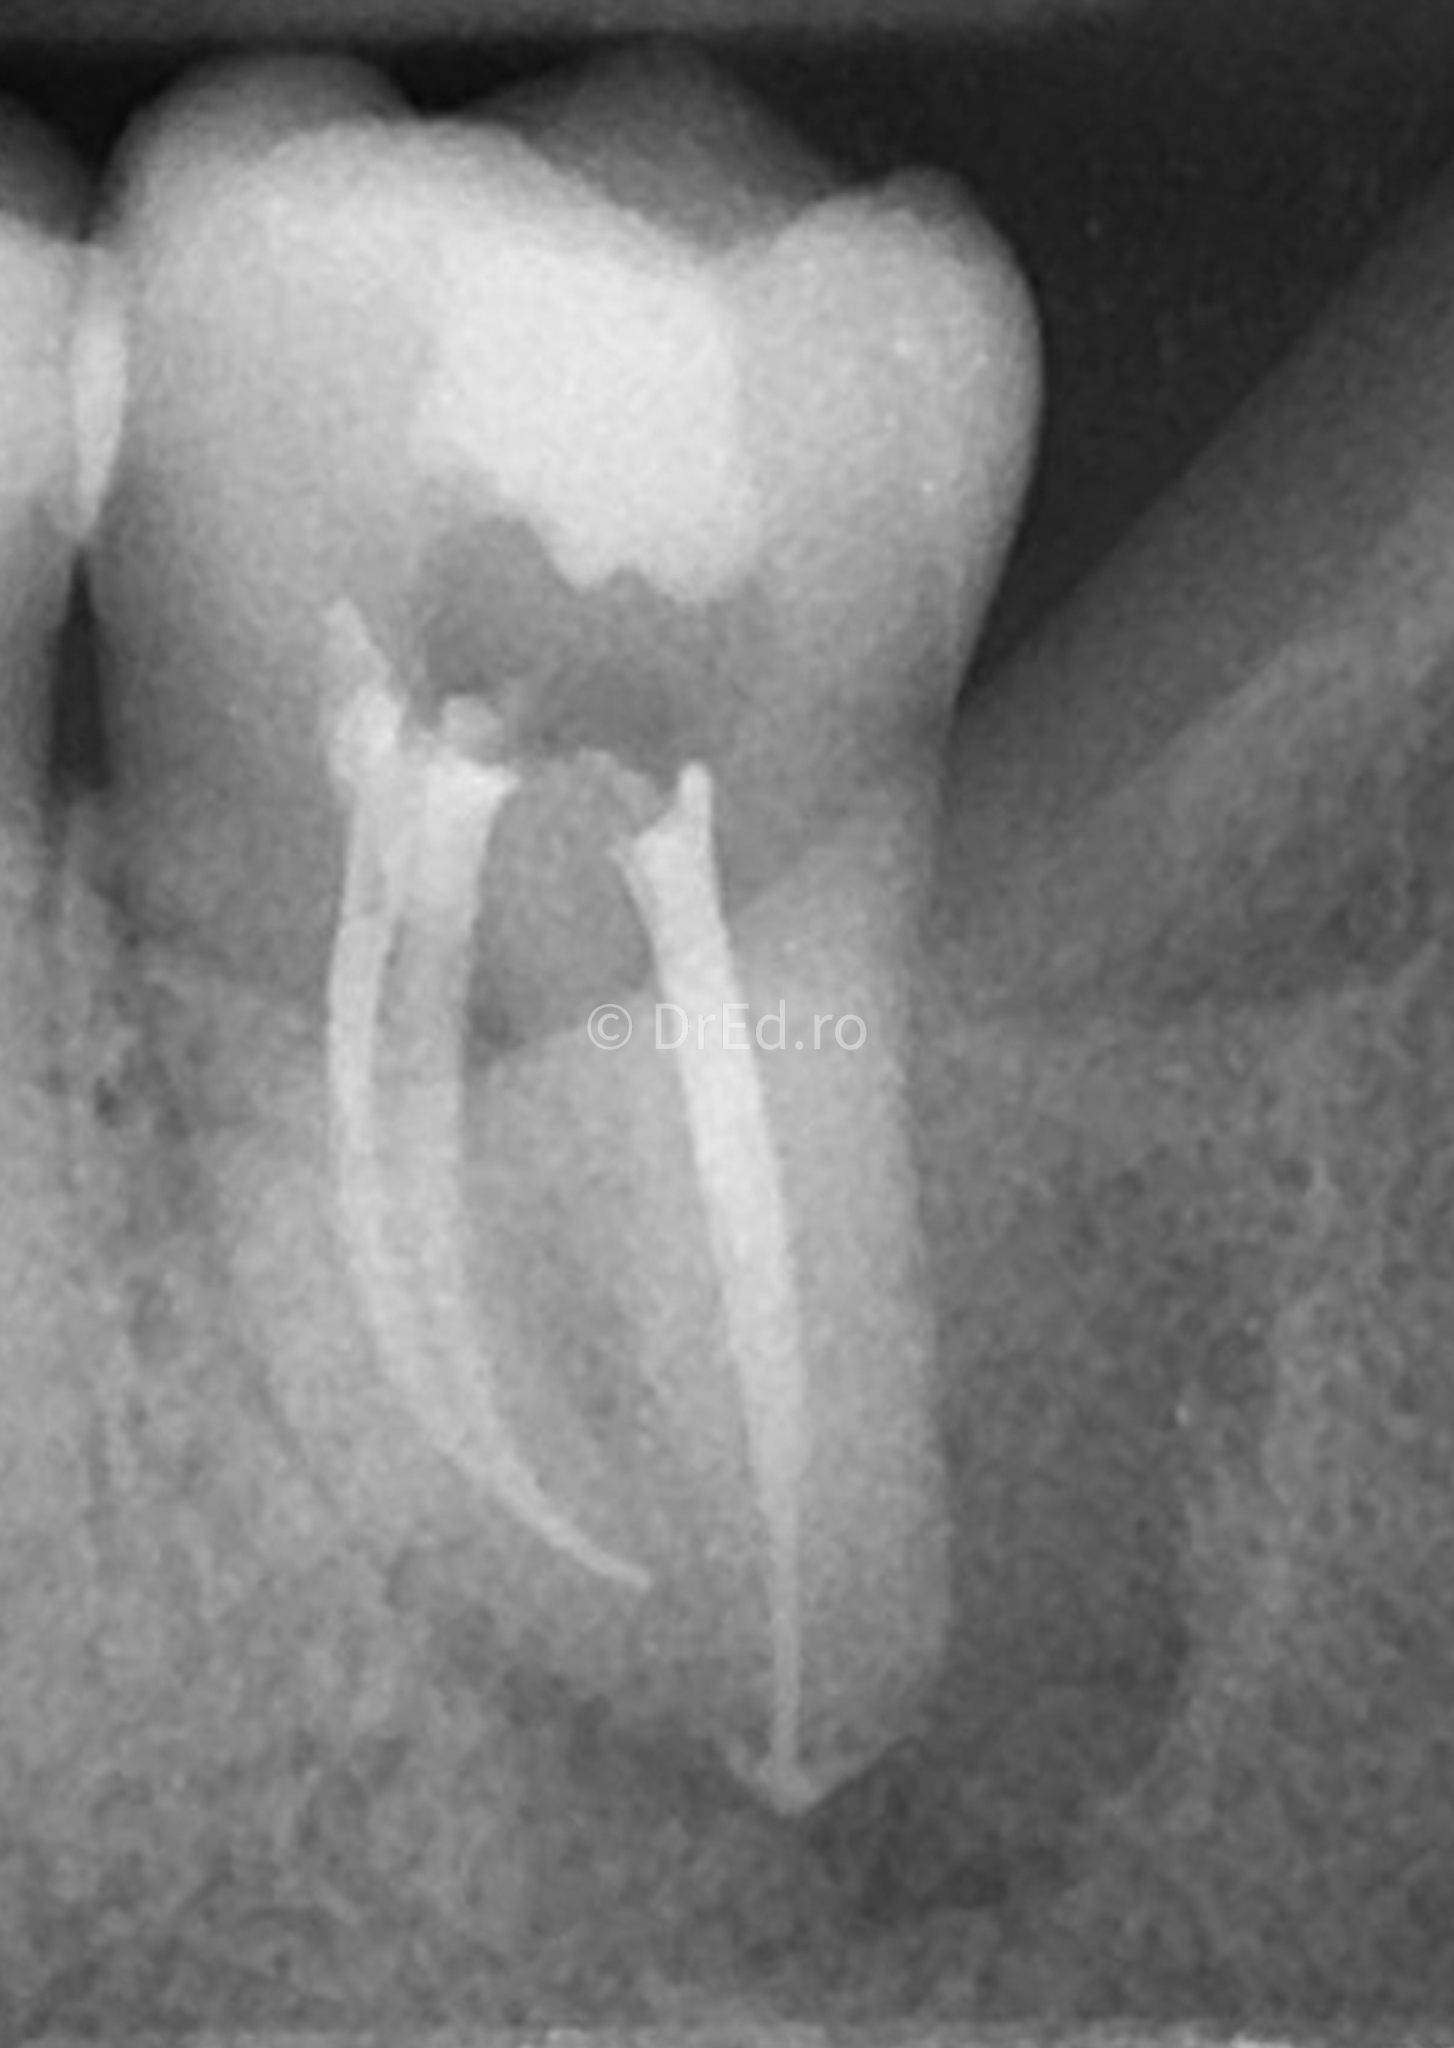

Galerie

Toate imaginile, fotografiile și radiografiile publicate pe acest site sunt protejate prin drepturi de autor și constituie proprietatea exclusivă a Dred.ro.

Aceste materiale sunt furnizate exclusiv în scop informativ și educațional și nu conțin date cu caracter personal sau informații care permit identificarea pacienților, în concordanță cu legislația privind protecția datelor cu caracter personal și GDPR.

Reproducerea, copierea, distribuirea, publicarea, transmiterea, modificarea sau orice altă utilizare, integrală ori parțială, a acestor materiale, în orice formă și prin orice mijloace, fără consimțământul prealabil scris al titularului drepturilor, este strict interzisă și poate atrage răspunderea civilă și/sau penală, în condițiile legii aplicabile privind drepturile de autor și protecția proprietății intelectuale.